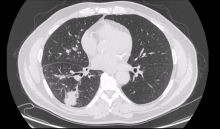

A 53-year-old man with no comorbidity was referred to the authors’ unit because of a multifocal wild-type adenocarcinoma of the right lung. A positron emission tomography scan was negative for metastasis and an endobronchial ultrasound-guided transbronchial needle aspiration staging of the mediastinum showed no lymph node involvement. After a multidisciplinary meeting, a right pneumonectomy indication was given. Preoperative evaluation showed no major contraindications.

The video-assisted thoracoscopic approach was biportal, using a 6 to 7 cm utility port at the fifth intercostal space, mandatory for the size of the lung and its extraction, and a 2 cm port for the camera at the eighth intercostal space. The lung parenchyma was completely altered because of the multiple foci of adenocarcinoma. First, the authors resected the pulmonary ligament and opened the mediastinal pleura to isolate the inferior and superior veins. The veins were transected with a mechanical stapler in the sequence shown in the video. Once transected, the authors noticed a small vein draining the S6 segment and had to divide this separately. Then they carefully cleared the pulmonary artery just over the pericardium and transected it using a mechanical stapler inserted from the inferior access. Again, the authors cleaned the bronchus and decided to close it with a TA™ stapler. The utility incision was sufficient to introduce that stapler, and they were able to obtain a bronchial stump as short as possible. A systematic lymphadenectomy was then performed and the bronchial stump was covered with a surgical glue.